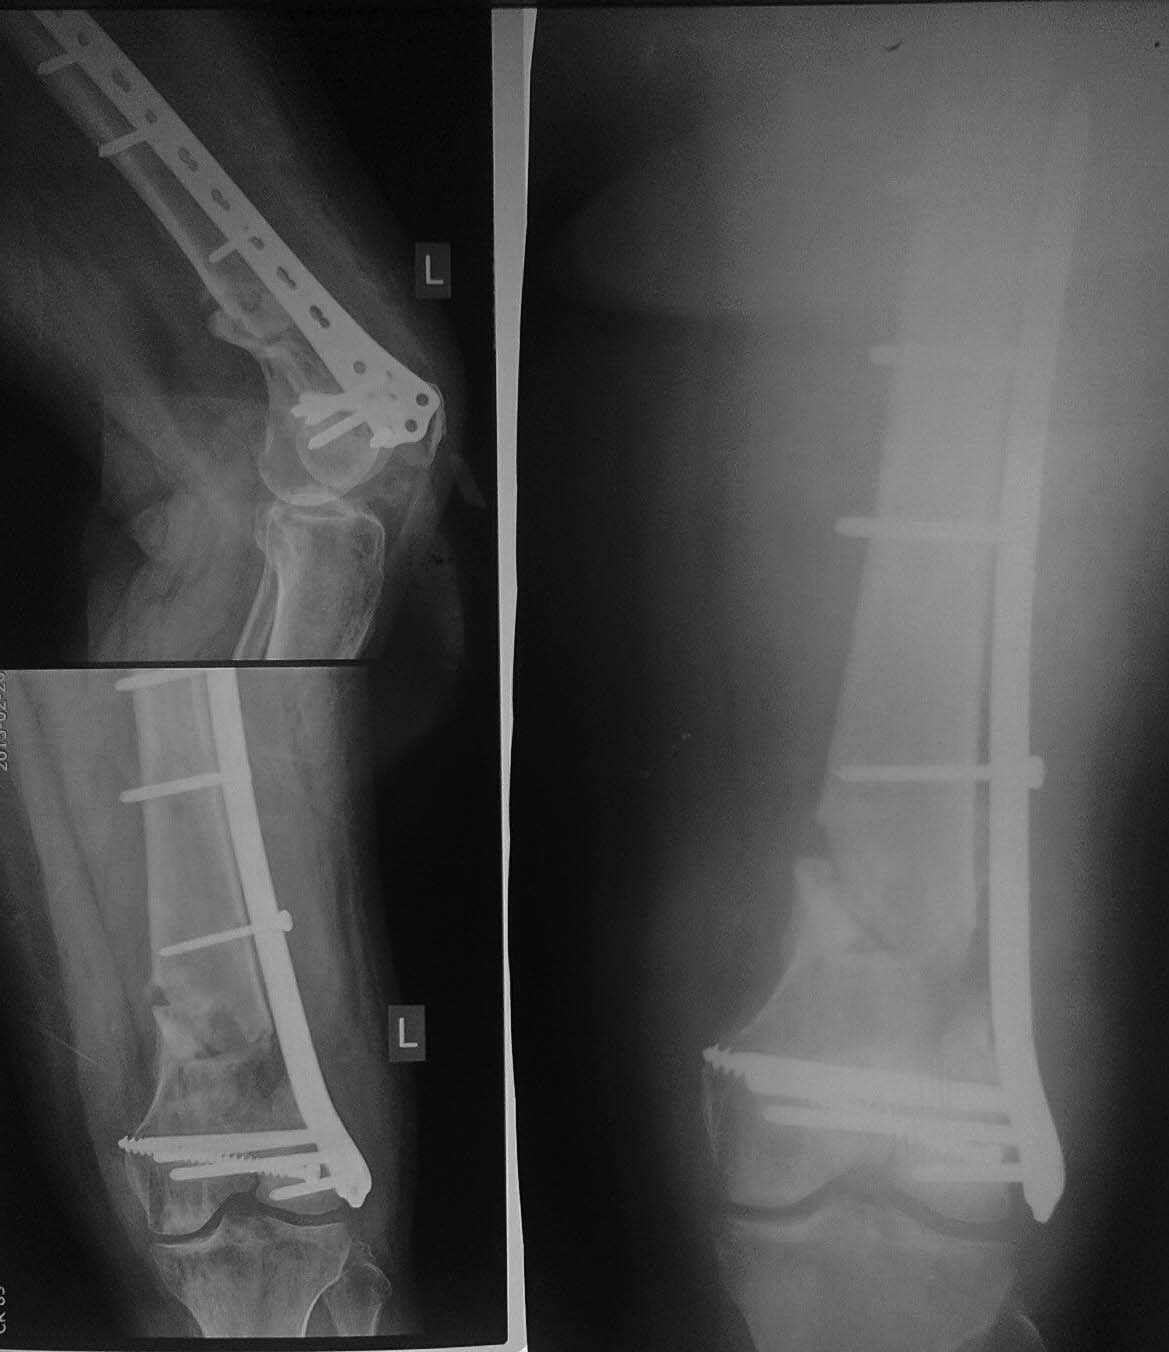

Операция 16.09.14.-Открытая репозиция мыщелков бедренной кости,

остеосинтез винтом, закрытая аппаратная репозиция, малоинвазивный

остеосинтез бедренной кости опорной мыщелковой пластиной на винтах с

угловой стабильностью с контролем под С-дугой(снимок 2).

Сегодня пришла на консультацию (снимок 3). С ее слов: в своей

поликлинике ей запрещают до сих пор нагрузку, аргументируя несращением.

Самостоятельно была на консультации в институте травматологии и

ортопедии в областном центре, где ей предложили выполнить реостеосинтез

с костной пластикой. Стоит ли торопиться с оперативным лечением или дать

походить с возрастающей нагрузкой- возможно произойдет полная

консолидация? Спасибо всем откликнувшимся!